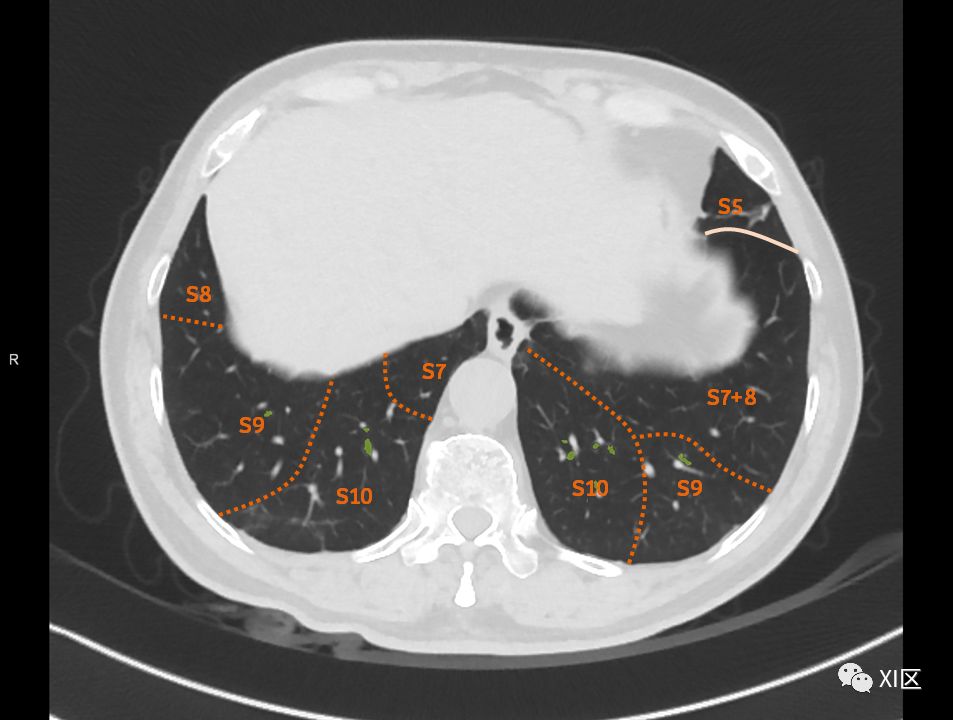

在进行肺的分段时,可以上下观察浏览,沿着相应气管的走形可以更容易准确地进行分段。

肺的断层分段示意图